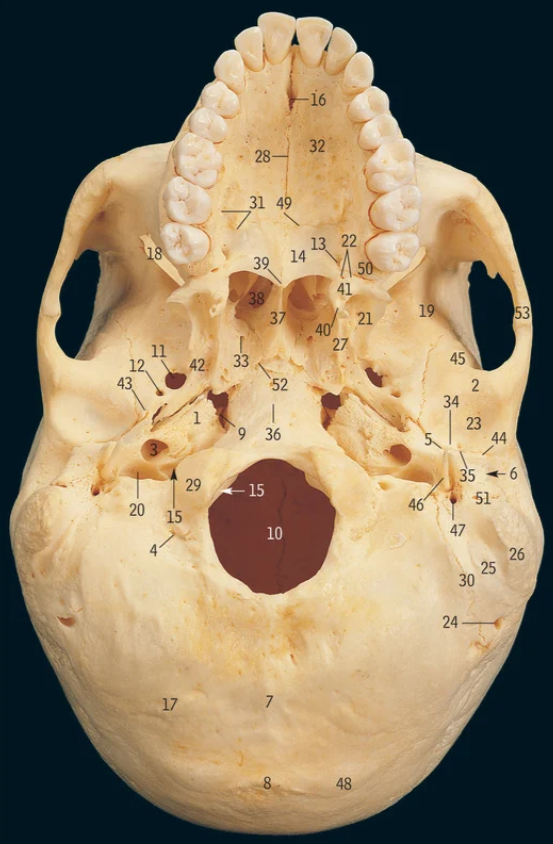

5

Cribiform plate

6

Crista galli

17

Greater wing of sphenoid bone

32

Lesser wing of sphenoid bone

38

Pituitary fossa

34

Optic canal

42

Superior orbital fissure

12

Foramen ovale

13

Foramen rotundum

14

Foramen spinosum

27

Hypoglossal canal

11

Foramen magnum

19

Superior nasal concha

Middle nasal concha

1

Ethmoidal air sinuses

Frontal air sinus

Lateral pterygoid plate

Medial pterygoid plate

Supra-orbital notch

29

Occipital condyle

48

Superior nuchal line

Which part of the ethmoid bone does the olfactory nerve exit

Which part of the ethmoid bone does the falx cerebri attach

Which part of the frontal bone does the supra-orbital nerve travel through

What cranial nerves travel through the superior orbital fissure

CN III/3, IV/4, V1/ophthalmic, VI/6

What travels through the hypoglossal canal

Hypoglossal nerve

What travels through the formen magnum

Spinal cord, accessory nerve

What muscles attach to the superior nuchal line

Occipitalis and trapezius

37

Zygomatic process of temporal bone

What muscle attaches to the zygomatic process of the temporal bone

18

Mastoid processÂ

Petrous part of temporal bone

28

Internal auditory meatus

9

Mandibular fossa

3

Carotid canal

46

Styloid process

47

Stylomastoid foramen

What is circle in blue

Inner ear

16

Middle ear

What is X

Foramen for emissary vein